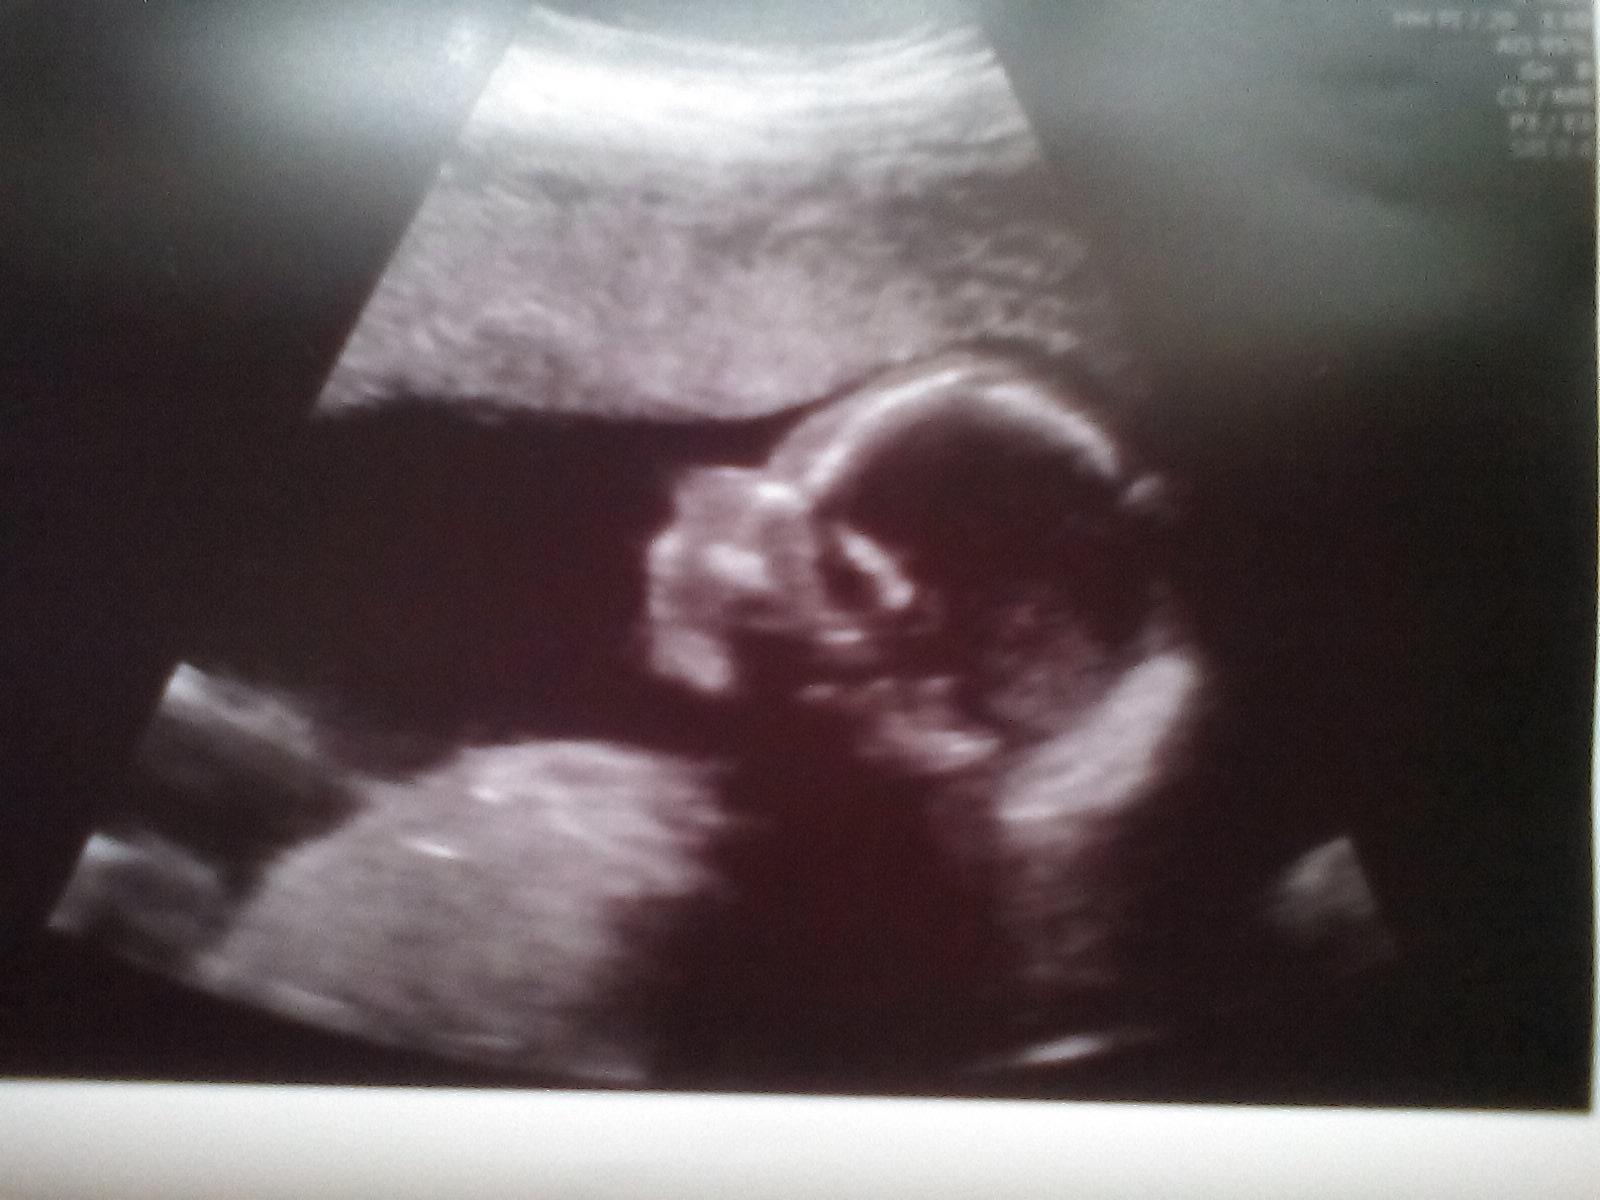

Ahoj holky, tak my jsme byli dneska na prvním UTZ po transferu. Viděli jsme nádherný tlukot srdíčka a odpovídáme 6+6tt ❤ Bylo to hrozně dojemné a doufám, že nejdřív za pár let se tam zase ukážeme 😎 Za nás tedy péče a profesionalita (a samozřejmě taky ceny 😀😀) v pronatalu na jedničku a doufám, že všem se brzy taky zadaří!!!!!!!!! 🤰

@salenas ta je krásná 😉